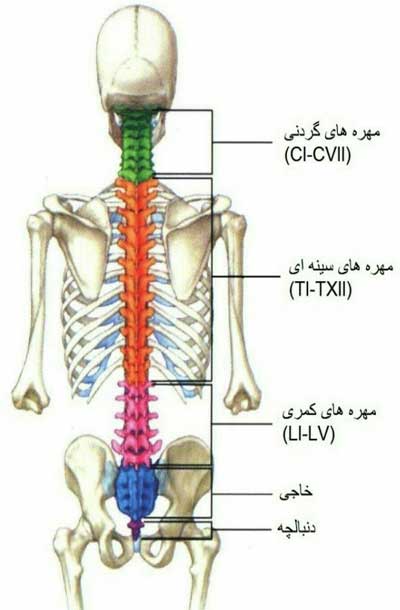

اسکلت داربست بدن است تمام قسمت های بدن روی اسکلت قرارگرفته اند بدن انسان از ۲۰۶ قطعه استخوان تشکیل شده است این استخوان ها طوری با نظم کنار هم قرار گرفته اند که انسان را قادر می سازد حرکات دقیقی داشته باشد. بدون اسكلت بدن مانند كرم شل و نرم است و این نوع شكل بندی نمیتواند. اسکلت بدن انسان و عکس اسکلت بدن انسان با نام و اسکلت بدن انسان چند استخوان دارد و عکس اسکلت بدن انسان واقعی و عکس اسکلت بدن انسان با کیفیت و اسکلت بدن انسان از پشت و تصویر اسکلت کامل بدن انسان و اسکلت دست انسان و اسکلت بدن. معرفی بدن انسان اسکلیت.

اسکلت داربست بدن است تمام قسمت های بدن روی اسکلت قرارگرفته اند بدن انسان از 206 قطعه استخوان تشکیل شده است این استخوان ها طوری با نظم کنار هم قرار گرفته اند که انسان را قادر می سازد حرکات دقیقی داشته باشد. اسكلت به بدن شكل میدهد. عکس اسکلت بدن انسان زن و مرد آناتومی ساتین 16 سپتامبر 2017.